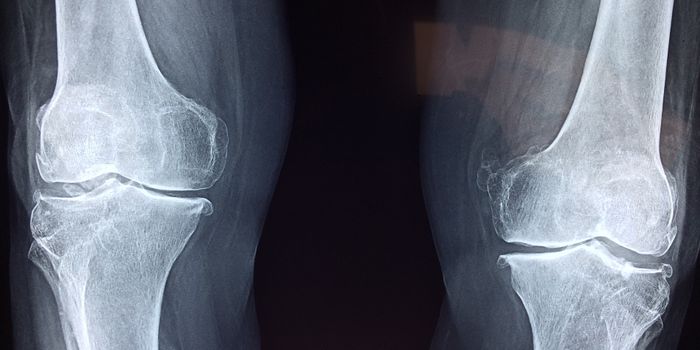

JAN 29, 2024Drug Discovery & DevelopmentOsteoporosis, a condition characterized by reduced bone density and an increased risk of fractures, is linked to systemi ...